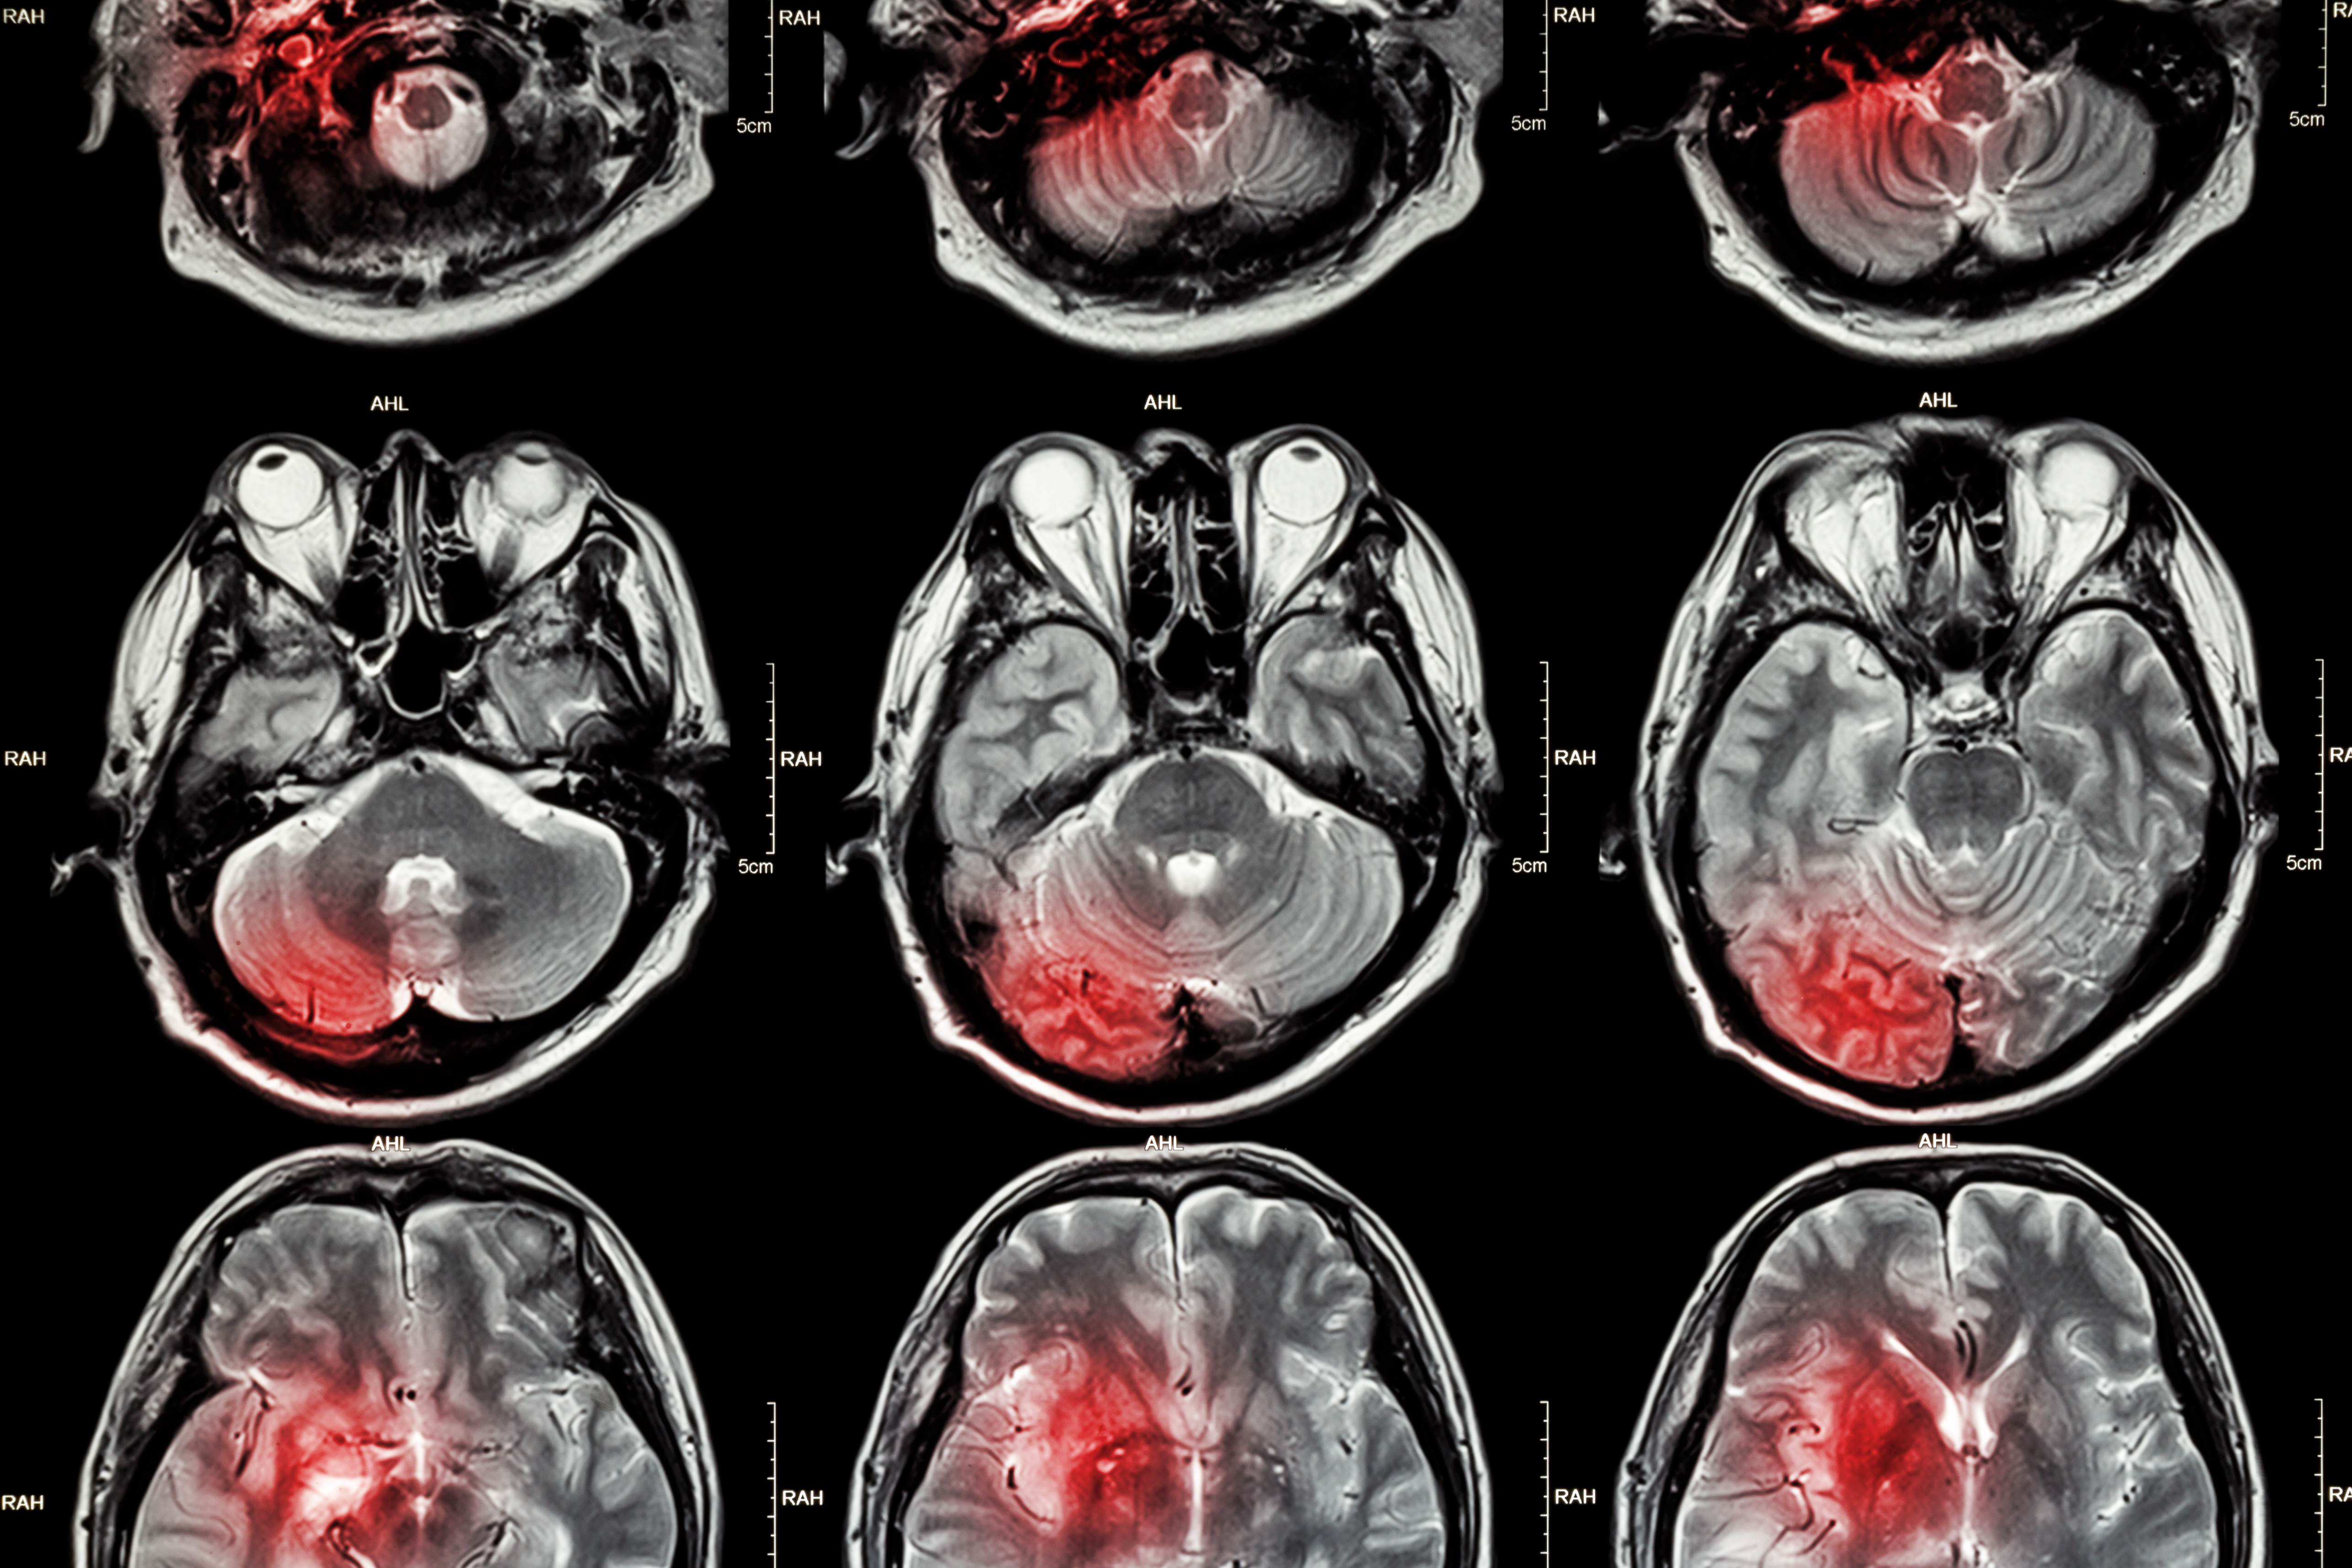

突发脑卒中如何抢得生命先机?专家带来的救命指南,人人须知!

公公脑干出血,老公指责我,我到底做错了什么

为什么中青年人群脑卒中的发病率正在逐年攀升?

今天有个患者在进行脑部检查的时候发现存在双侧额顶叶白质异常